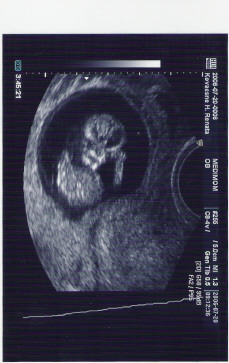

Amugy meg mindig semmi vizsgalat nem volt. Megmertek a vernyomasom, a testmagassagom, es testsulyum. Fel se tunt nekik, hogy fogytam 2 kilot, amiota a korzeti mert meg, mivel a vedonok merlege pont 2 kiloval tobbet mutat. A vernyomasom pont jo volt, de csak azert, mert izgultam. Kulonben alacsony szokott lenni. Valamikor annyira, hogy szinte lebegek. Ket csaj volt, de egyik se az, aki a vedonom lesz, mert o most pont szabin van. Aranyosak voltak. Kerdezte az egyik, amikor toltotte ki a papirjaimat, hogy ki a haziorvosom. Mondtam neki, hogy kinel voltam a multkor, de szoltam neki, hogy tobbet viszont nem szandekozom latni a holgyet. Rendes volt, mondta, hogy nyugodtan valaszthatok es beirta egy masik doki nevet a papirjaimra. Azt mondta, hogy ez a doki nagyon kedves. Nekik is emlitettem, hogy a szemeszem csaszarmetszest javasolt. Az egyik vedono (aki huszoneves lehet) csodalkozott, de a masik, az idosebbik mondta, hogy igen, van ilyen. Kerdeztem, hogy az ugy jo-e, ha Magyarorszagrol a szemeszemtol hozok errol papirt angolul. Mondtak, hogy termeszetesen. Szoval, azt hiszem, minden ok lesz. Csak a haziorvosom, az az indiai picsa volt olyan sotet. Mar bocs, hogy ilyen rondan hivom, de ez illik ra a legjobban. Meg mindig nem hiszem el, hogy ilyen hianyos tudassal praktizalhat valaki. Egyszeruen felhaborito. Bar szerintem a vedono se sokra tartja, mert egybol megertoen mondta, hogy nem muszaj tobbszor hozza mennem es rogton javasolt egy masikat.